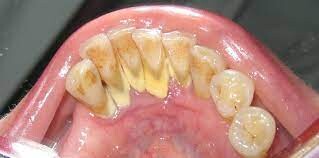

When plaque builds up in your mouth, it can turn into an even greater dental health threat: calculus. This formation, also known as tartar, is a calcified mass that adheres to your teeth. Calculus is classified as either supragingival or subgingival, depending on its location on your teeth. If left unremoved, subgingival calculus can lead to gum disease and tooth loss.

An article published in the International Journal of Dental and Health Sciences (IJDHS) explains that plaque, which is a sticky film of bacteria that constantly forms on your teeth, can mineralize due to the exchange of calcium and phosphate ions present in your saliva. This process is what creates calculus, a hard mass of bacteria stuck to your tooth surfaces.

Plaque can harden into calculus in as little as four to eight hours. The average length of time for mineralization, however, is 10 to 12 days. Calcification times can vary from person to person, depending on their salivary pH and the amount of calcium and other substances in their saliva. Once calculus forms, it then attracts more plaque, which in time can become another layer of calcified material.

Characteristics of Subgingival Calculus

Tartar that accumulates on your teeth above the gumline and is easily seen by your dentist or dental hygienist is called supragingival calculus, according to the IJDHS article. But the tartar that forms below the gumline — and is therefore not immediately visible — is known as subgingival calculus. This type of calculus is usually dark brown to greenish black in color and can be detected with a dental instrument called an explorer.

It's important to note that, while you can clean plaque off your teeth with brushing and flossing, hard tartar can only be removed by a professional cleaning, explains the American Academy of Periodontology (AAP). Your dentist or dental hygienist uses special instruments that are designed to remove the calculus.